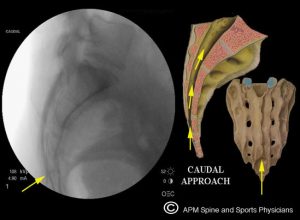

- Caudal ESI:this injection is placed through a small opening (sacral canal) just above the tailbone. It is a very safe injection with very little risk and is most effective with central disc herniations at L5-S1 and L4-5 as well as spinal stenosis at these levels.